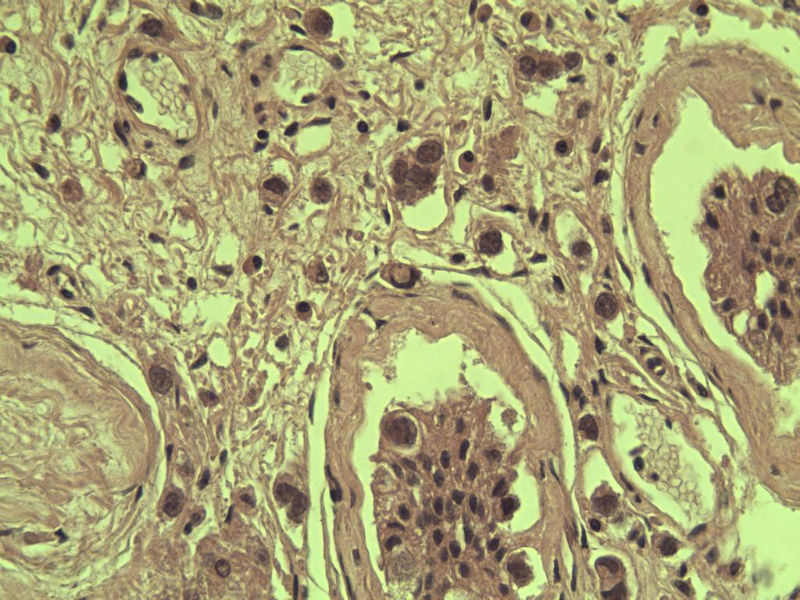

男 27岁 腹腔隐睾 5*3*2 cm, 切面灰红灰黄、实性、质中,请各位老师看看,是精原细胞瘤吗?感觉不像.腹腔隐睾图1

典型的精原细胞瘤,隐睾易恶变